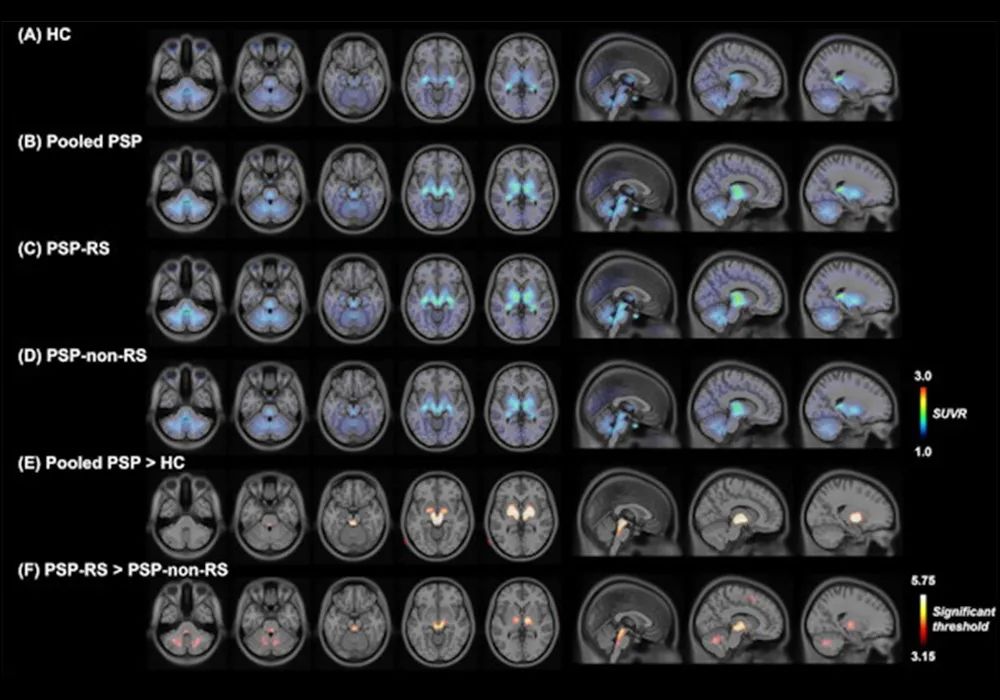

進(jìn)行性核上性麻痹患者的F-18 Florzolotau PET圖像。這些圖像說明了健康對照(HC)組(圖A)、整個患者群組(圖B)以及PSP-Richardson綜合征(RS)(圖C)和PSP-non-RS(圖D)組中的F-18 Florzolotau攝取。與HC組相比,PSP患者顯示主要在蒼白球-黑質(zhì)-路易體軸的結(jié)合顯著增加(圖E)。雖然兩個患者組的示蹤劑累積模式相似,但PSP-non-RS患者的結(jié)合強(qiáng)度明顯較低(圖F)。A-D圖中的顏色條表示標(biāo)準(zhǔn)化攝取值比率(SUVR),而E-F圖中的顏色條表示來自體素方面比較的閾值。圖片和說明由歐洲核醫(yī)學(xué)和分子影像雜志通過CC BY 4.0提供。